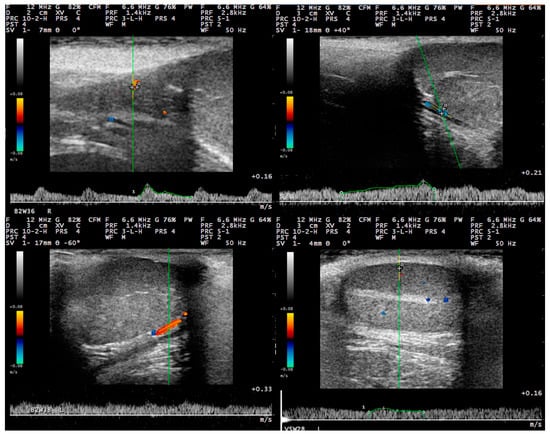

3.2. B-Mode Examination

3.3. Pulsed-Wave Doppler

4.2. Differences in the Findings between the Regions of the Testis